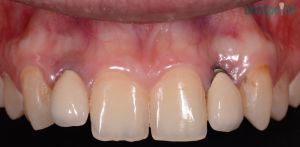

Régi implantátumok cseréje, fémmentes koronák felhelyezése

Fiatal hölgy páciensünk a 10 évvel ezelőtt behelyezett implantátumainak csontpusztulása és ínyének visszahúzódása miatt keresett fel minket. A régi implantátumok eltávolítását követően újakat helyeztünk be, és ínyplasztikai kezeléssel, valamint cirkónium egyéni implantátum fejekre készített e.max fémmentes kerámia koronákkal adtuk vissza páciensünk elégedett mosolyát.

1) Kiindulási helyzet

2) Implantátumok és koronák cseréje után